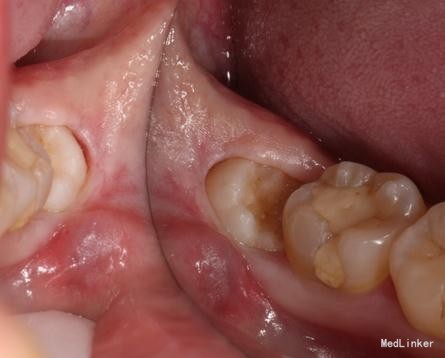

检查: 18.28颌面龋坏,质地软,牙颈部脱矿,叩诊(-),不松动。 37玻璃充填物,叩诊(-),不松动,冷热刺激正常。 38近中水平阻生,牙龈无红肿,叩诊(-),探诊有盲袋,盲袋内食物碎屑。 47缺失多年,48近中向移位,间隙1mm,叩诊(-),不松动。

治疗计划:18、28,38拔除。 37重新充填。 48观察。 治疗:28局麻下拔除。 38阻滞下拔除。